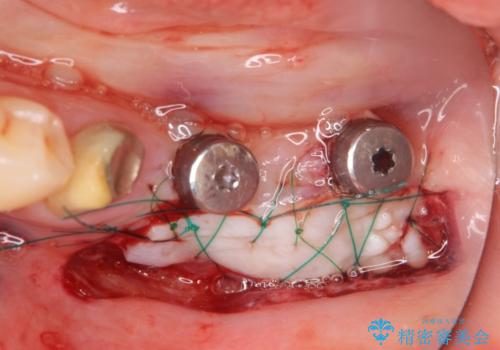

精査をしたところ、歯の破により残すことが難しい状況で、親知らずと共に抜去を行いインプラントによる機能回復を計画します。

- 110万円(インプラント×2・チタンカスタムアバットメント×2・ジルコニアクラウン×3・仮歯×3 ・遊離歯肉移植術)費用は治療当時の料金となります

インプラント周囲のお掃除のしやすさを高め、長期的な予後を見込むために、遊離歯肉移植術を行っています。